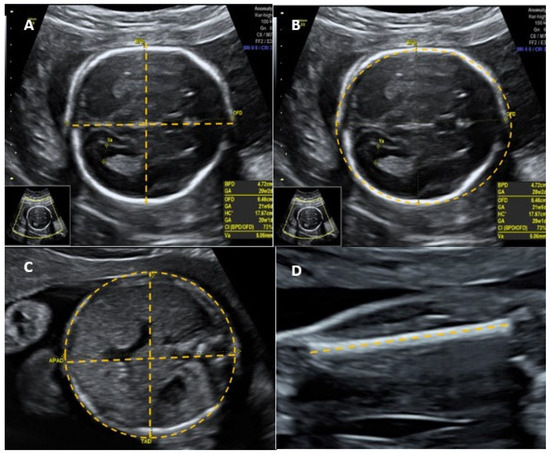

The following parameters were considered adverse perinatal outcomes: Apgar score at the 1st minute < 7, Apgar score at the 5th minute < 7, neonatal intensive care unit (ICU) admission, maternal ICU admission, neonatal death in the first 48 h, postpartum hemorrhage, and maternal death. The presence of at least one adverse perinatal outcome was considered a composite adverse perinatal outcome. To consider the quality of the cephalic pole image as adequate, all of the following parameters had to be observed during BPD and HC measurements: plane between cerebral hemispheres symmetrical, thalamus visible, cavum of the septum pellucidum visible, cerebellum not visible, magnification of the fetal head occupying at least 50% of the screen, caliper correctly positioned on the outer edge of the anterior wall of the cephalic pole and on the outer edge of the posterior wall of the cephalic pole [3] (Figure 1A). To assess the HC, the calipers were positioned in the external–external position [2] (Figure 1B).

In order to consider the image quality of the fetal abdomen as adequate and to verify the AC measurement, all of the following parameters should be observed: the axial plane of the abdomen should be as rounded as possible while maintaining its symmetry; the stomach should be visible; the portal sinus should be visible; the kidneys should not be visible; magnification of the abdomen should occupy at least 50% of the screen; the calipers should be correctly positioned; the outer edge of the skin should be posterior to the spine and the outer edge of the skin of the anterior wall of the abdomen [2,3] (Figure 1C). For the image quality of the FL measurement to be considered adequate, all of the following parameters should be observed: there should be clear visualization of the end of the bone diaphysis, the angle between the sound beam and the femur should be between 45° and 90°; the magnification of the femur should occupy at least 50% of the screen; the calipers should be correctly positioned between the end of the two diaphyses [2,3] (Figure 1D).

Figure 1. Measurements of biparietal diameter (BPD) (A), head circumference (HC) (B), abdominal circumference (AC) (C), and femur length (FL) (D) according to the International Society of Ultrasound in Obstetrics and Gynecology (ISUOG) guidelines.